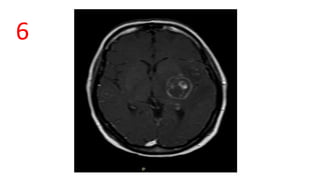

Eccentric target sign (cerebral toxoplasmosis)

• pathognomonic

• postcontrast MRI/CT as a ring enhancing lesion with an eccentrically

located enhancing mural nodule.

• seen in less than one-third